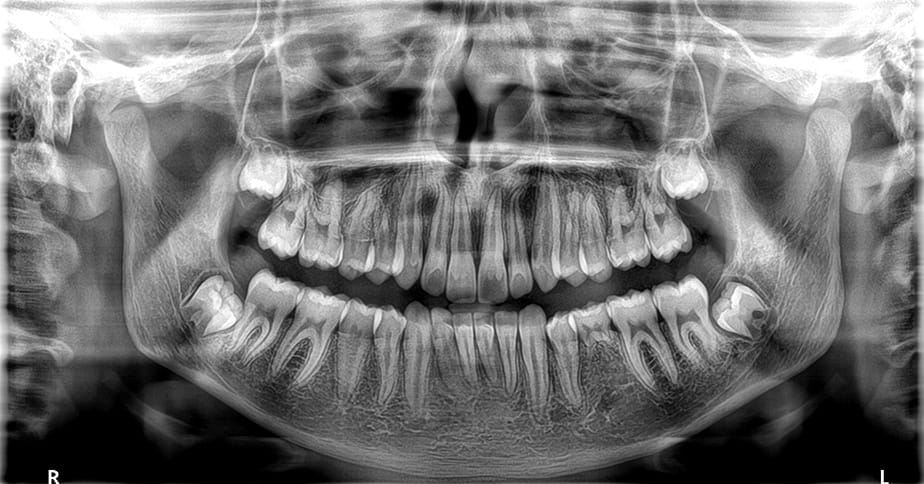

SmartAuto Pan analyserer patientens kæbeform i 3D og beregner automatisk den optimale eksponering og strålebane. SmartAuto 3D lader operatøren definere FOV-positionen på en lavdosis scout-optagelse — og beregner resten selv. Resultatet er konsistente, højkvalitetsbilleder uanset operatørens erfaring.

Tomosharp-algoritmen rekonstruerer automatisk de skarpeste panoramabilleder, selv ved uperfekt positionering. CS MAR reducerer metalstøj fra implantater og fyldninger i CBCT-volumen, så billedet er klart og fortolkbart — selv i de mest komplekse cases.